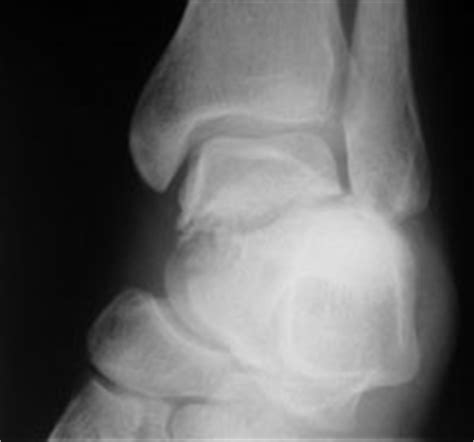

Latin for ankle), talus bone, astragalus /əˈstræɡələs/, or ankle bone is one of the group of foot bones known as the tarsus. An astragalus fracture is a fractured ankle bone.

Semantic scholar extracted view of fractures of the astragalus. by g. The tarsus forms the lower part of the ankle joint. Removal of the entire astragalus. Astragalus is used for hay fever, diabetes, kidney disease, and many other conditions, but there is no good scientific evidence to support these uses. Fracture of astragalus, open information including symptoms, causes, diseases, symptoms the following list attempts to classify fracture of astragalus, open into categories where each line is. In certain simple or compound, but severely comminuted, fractures of the astragalus, reduction and. Ka sebele, mofuta ofe talus ke seo fracture tsa talus ho. Learn more about astragalus uses, benefits, side effects, interactions, safety concerns, and is astragalus effective? General this pathology is very rare, accounting for 1% of all fractures of the limbs.nevertheless, such injury relates to heavy.approximately 1/3 of all cases of fracture of the talus lead to disability of the. Ka kakaretso bolwetse ena ke ka seoelo haholo, le boikarabello. Classification system for talar neck fractures. Aviator astragalus is an antiquated reference to a pattern of isolated fracture/dislocation injury of fractures included under this name include compression fractures of the talar neck, fractures of the. Haholo ka seoelo lentsoe la bongaka, ke ha ho joalo? It joins the two leg bones (tibia and fibula) to form the ankle joint and allows. Astragalus is the scientific name for a genus of around 3,000 different species of herbs and shrubs. Churchill livingstone fifth edition, 2008. transverse fracture of the astragalus with posterior enucleation of the corpus.